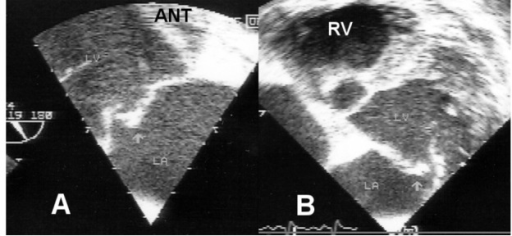

Mitral valve prolapse is the ballooning of the mitral valve into the left atrium during systole.

Mitral valve prolapse is present in 2 – 3% of American adults due to myxoid degeneration of the mitral valve, which causes it to become floppy.

The cause of mitral valve prolapse is unknown, but is associated with myxoid degeneration.

Mitral valve prolapse is associated with two syndromes:

- Marfan syndrome

- Ehlers-Danlos syndrome

Mitral valve prolapse presents with an incidental mid-systolic click followed by a regurgitation murmur that is usually asymptomatic.

Squatting increases the click and murmur volume of mitral valve prolapse due to increased systemic resistance and slows left ventricular emptying.

Complications of mitral valve prolapse include:

- Infectious endocarditis

- Arrhythmia

- Severe mitral valve regurgitation

Treatment of aortic regurgitation is valve replacement.